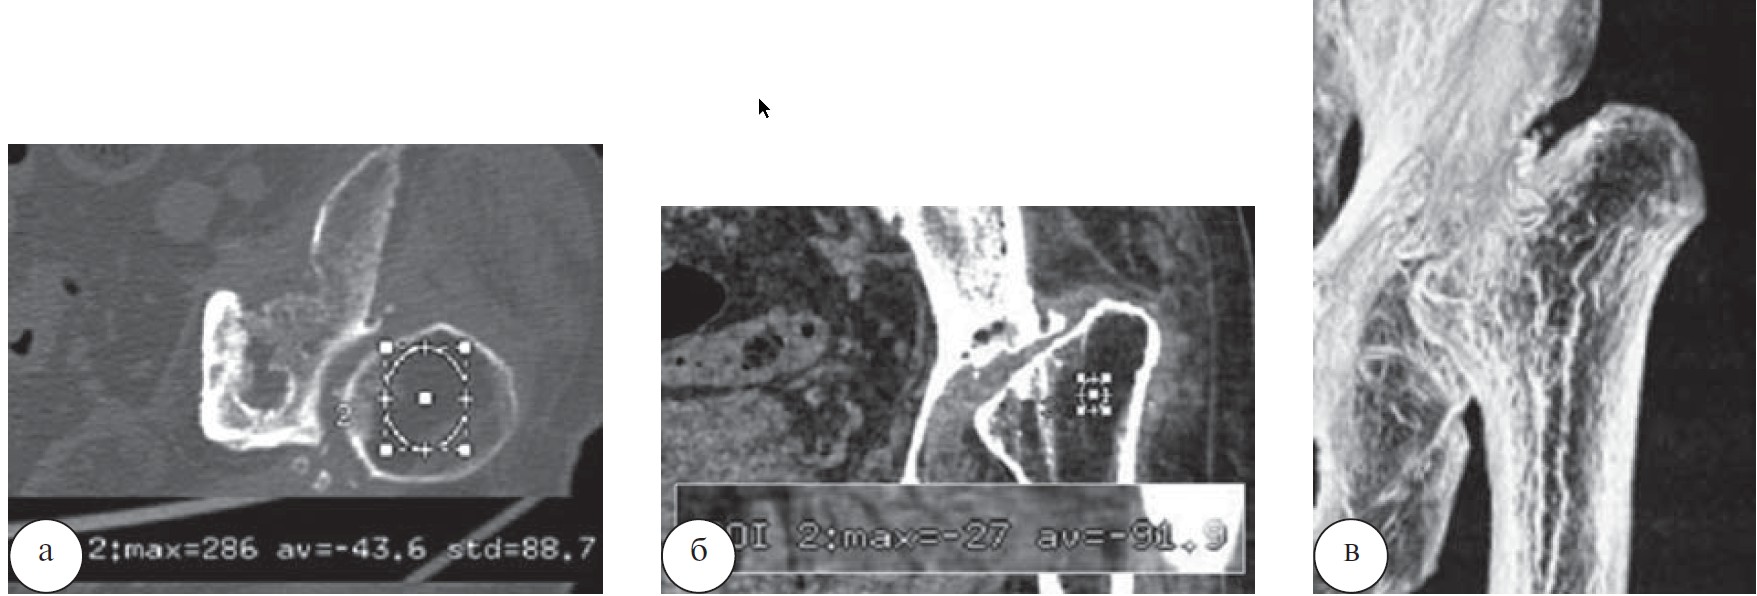

При наличии подострой формы хронического остеомиелита после ревизионного эндопротезирования правого тазобедренного сустава на фистулограммах у 17 больных определялись затеки контрастного вещества в мягкие ткани по наружной поверхности бедра. На аксиальных срезах тазобедренного сустава, после удаления эндопротеза, плотность крыши вертлужной впадины, области малого вертела значительно снижена, корковая пластинка имела неравномерную толщину и плотность. В области малого вертела плотность кости составляла 98,17±9,70 HU, в области крыши вертлужной впадины - 25,36±10,72 HU (рис. 4).

Рис. 4. Рентгенограмма (фистулограмма) тазобедренного сустава больного К., 74 года (а). Перипротезная инфекция.

Хронический остеомиелит. МСКТ тазобедренного сустава: б — аксиальные срезы на уровне вертлужной впадины и малого вертела; в — аксиальный срез на уровне диафиза.

При гистологическом исследовании, учитывая наличие заметного представительства сегментоядерных лейкоцитов в межтрабекуляных пространствах губчатой порции исследованного материала, данное наблюдение расценивали как хронический остеомиелит в подострой форме (рис. 5).

Рис. 5. Губчатый костный фрагмент: а — гнойный экссудат в межтрабекулярном пространстве. Окраска гематоксилином и эозином. Ув. 500; б — остеонекроз компактной кости, очаги патологической минерализации. К краям костных фрагментов примыкают поля грануляционной ткани с признаками фиброзирования. Ув. х 125.

У больного П., 69 лет после эндопротезирования левого тазобедренного сустава развился хронический остеомиелит. После удаления эндопротеза и резекции головки и шейки бедренной кости, проведенного лечения отмечена ремиссия. По данным МСКТ отмечался дефект проксимального отдела бедренной кости, смещение ее в проксимальном направлении, деформация суставной впадины, умеренный отек и рубцовые изменения мягких тканей. Выражен остеопороз проксимального отдела бедренной кости (плотность в отрицательном спектре шкалы Хаунсфилда). Аналогичная ситуация имела место у 8 больных (рис. 6).

Рис. 6. МСКТ тазобедренного сустава больного П., 69 лет: а — аксиальный срез, плотность в области большого вертела (—43,6 HU); б — MPR, отсутствие характерного трабекулярного строения в межвертельной области, плотность — (—91,9 HU); в — VRT.